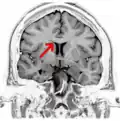

Corpus callosum

Corpus callosum from above, front part at the top of the image